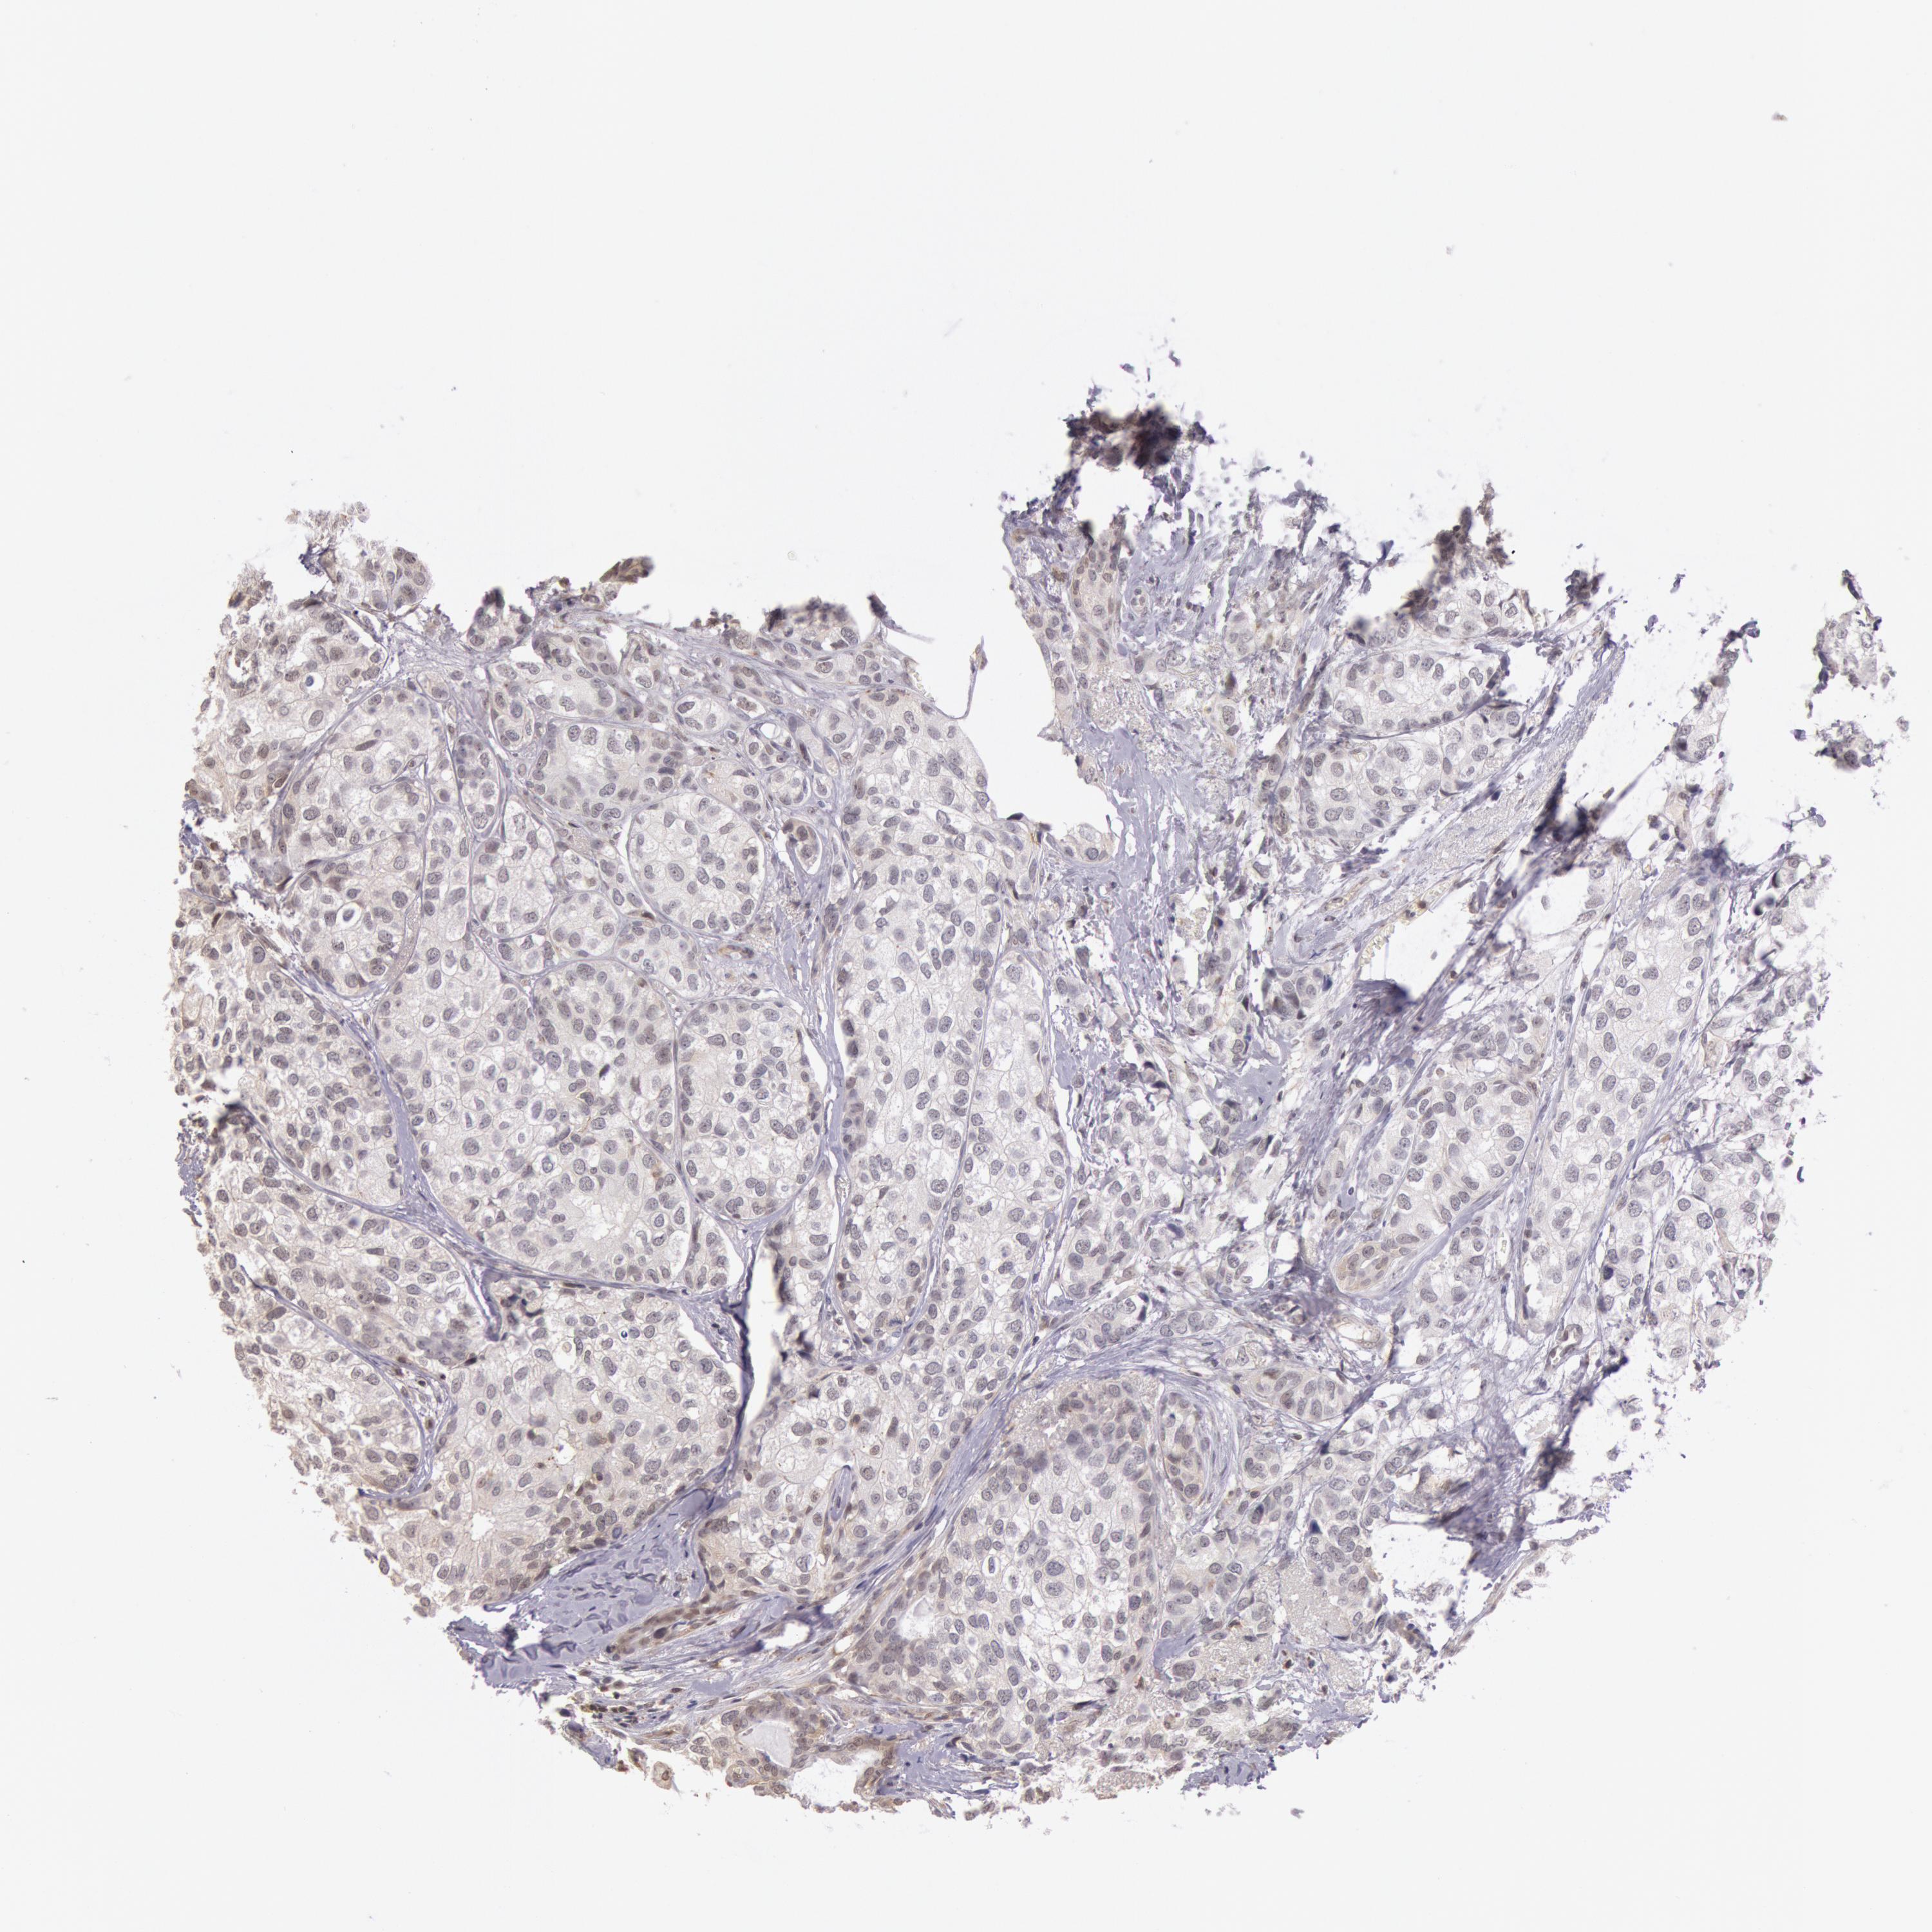

CANCER BREAST CANCER Show tissue menu

BRCA TCGA BRCA VALIDATION PROTEIN EXPRESSION

ANTIBODIES

AND

VALIDATION